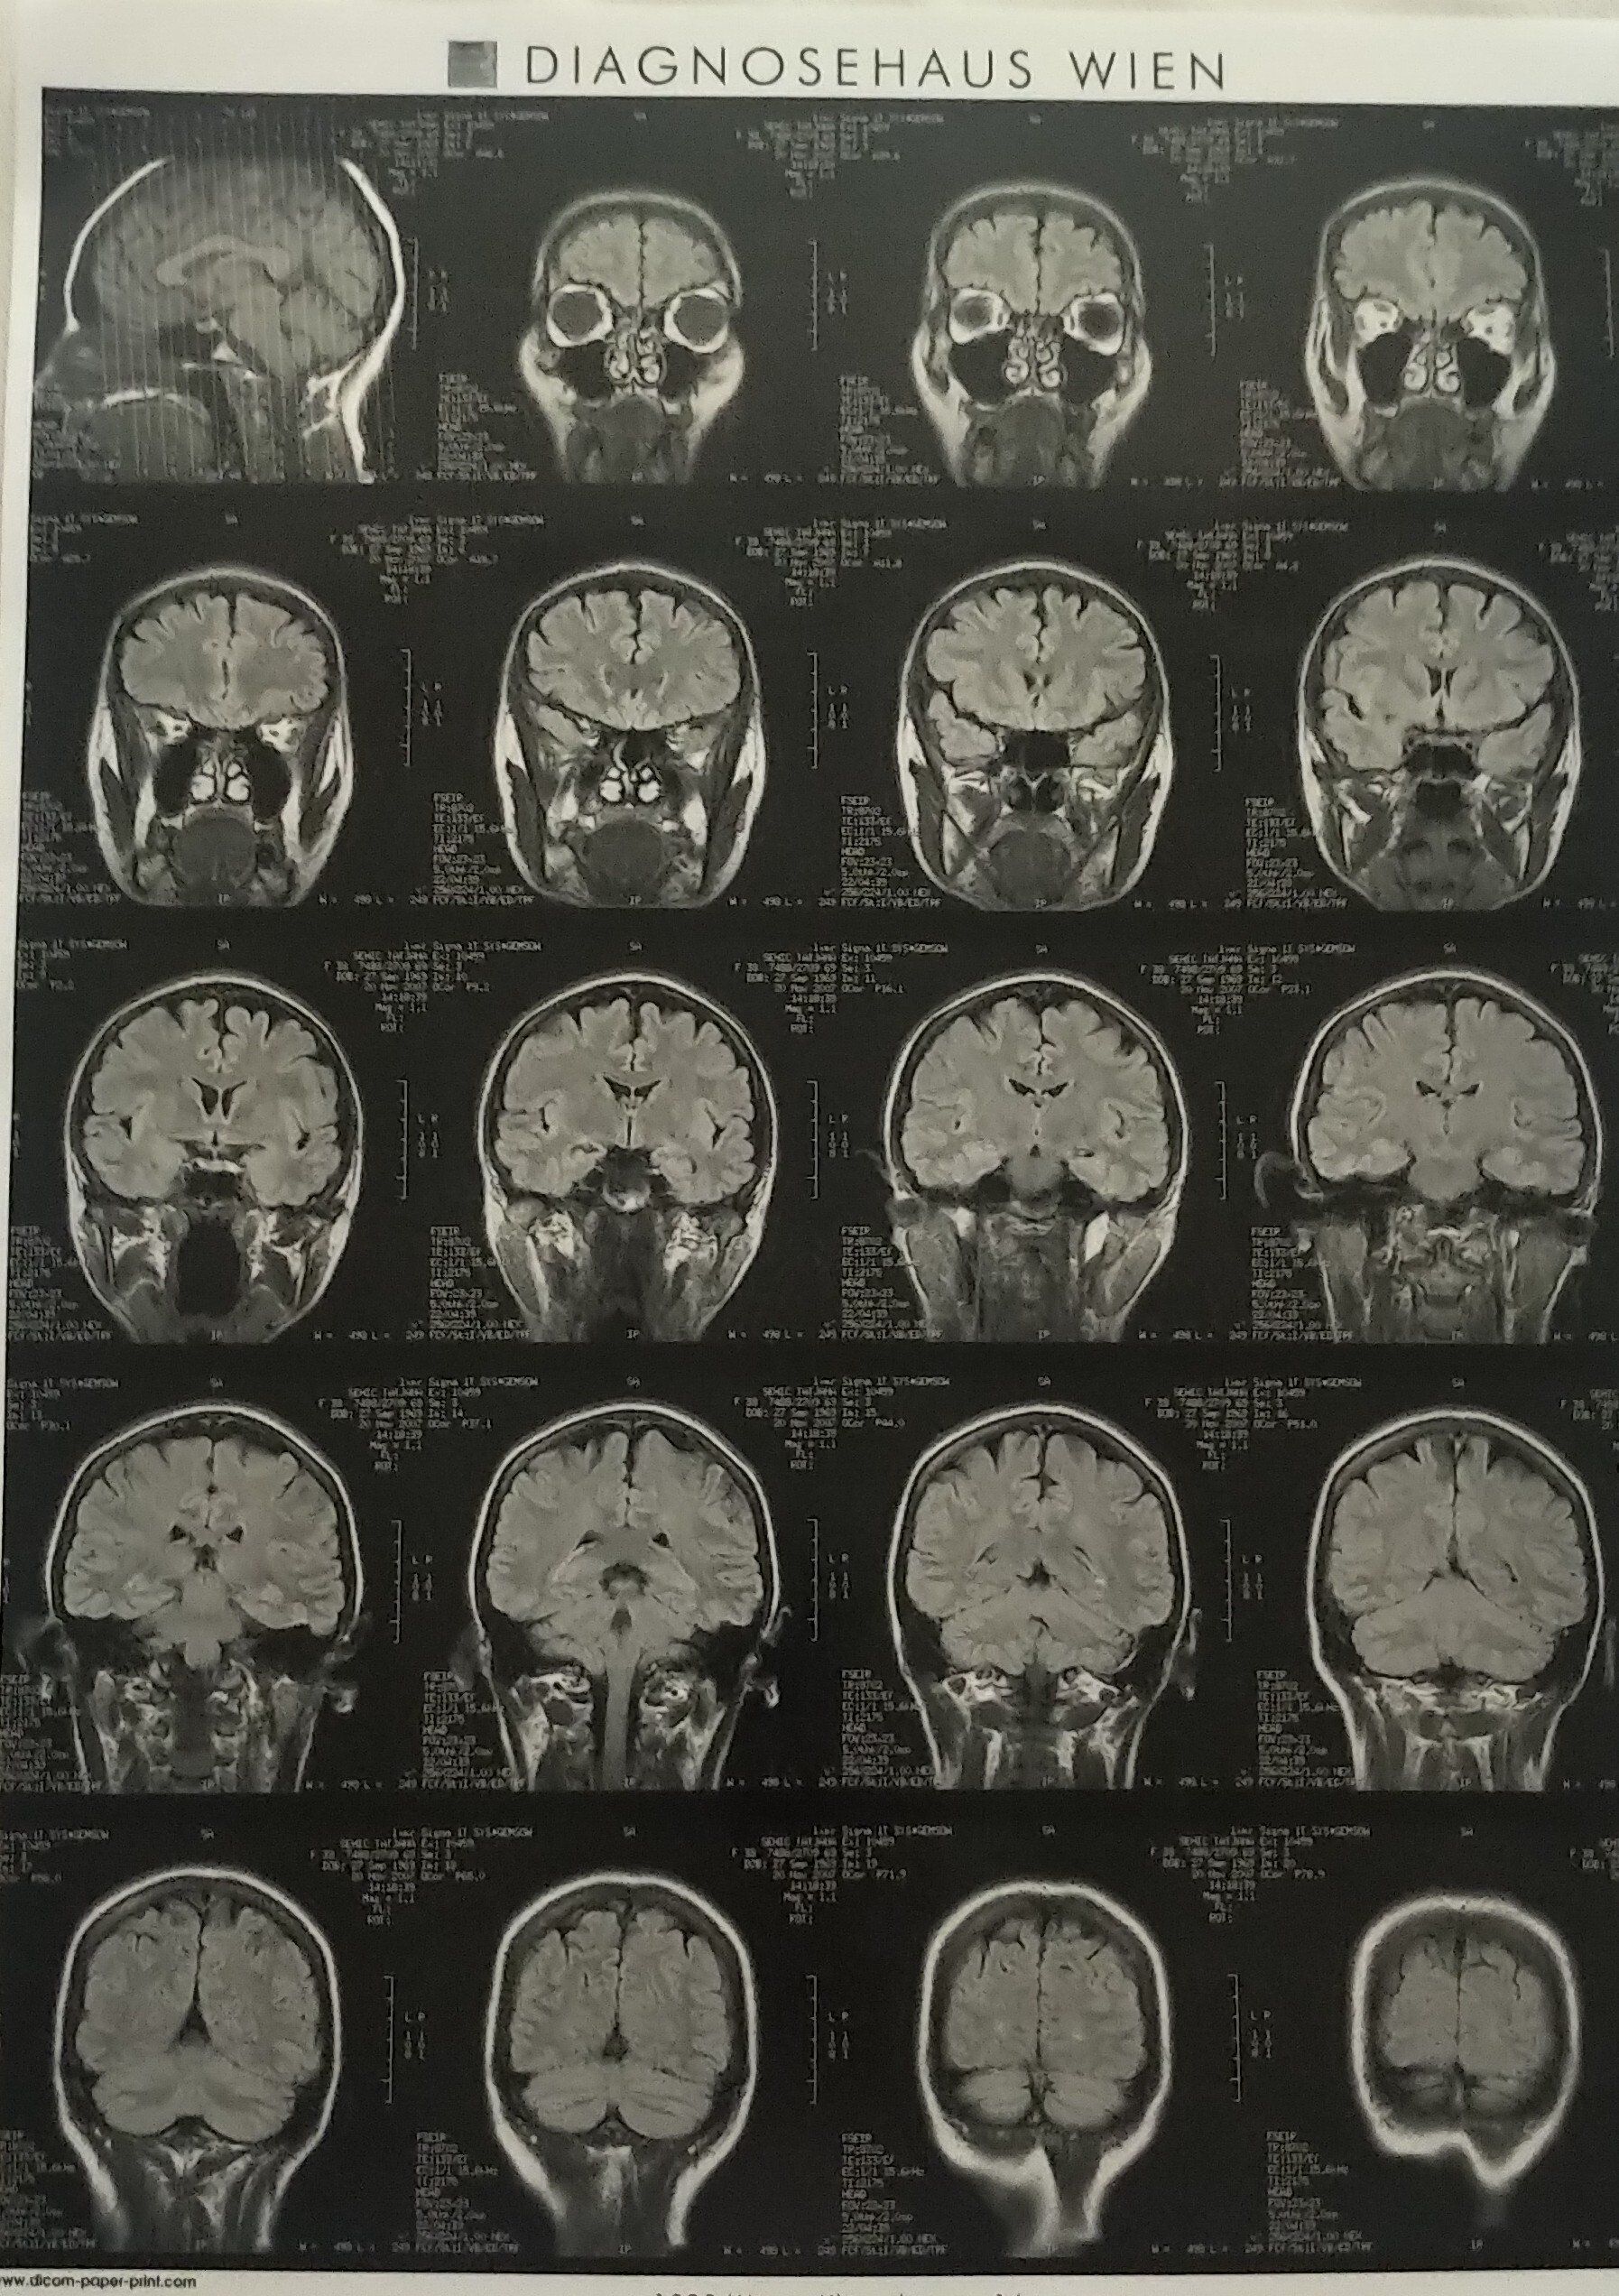

Moj mozak MR- snimak, (tajno) razmišljajući na hrvatskom, njemačkom, engleskom, o

"kiši"

prije nekoliko godina, prilikom provjere uzroka napetosti u potiljku

Corpus callosum sastoji se od oko 200 milijuna aksona koji međusobno povezuju dvije moždane hemisfere, poznate kao lijeva hemisfera i desna hemisfera. Primarna funkcija Corpus Callosum je integrirati motoričke, senzorne i kognitivne performanse između dviju moždanih hemisfera (moždane kore), omogućujući komunikaciju između njih.